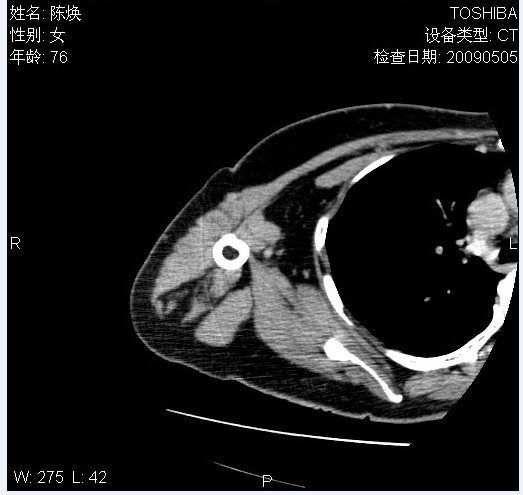

标题: CT19811:女,76岁,右上臂肿物1个月 [打印本页]

标题: CT19811:女,76岁,右上臂肿物1个月

使用了造影剂,可惜效果不太好

右肱骨上段软组织内见梭形低密度影,边界清楚,最长径约54mm.

病理结果:脂肪瘤。术中见肱骨骨膜受侵,有出血,量不详。

当时诊断意见:右肩三角肌内蔓状血管瘤(先天性动静脉瘘)。

本人对病理结果有个疑问:单纯的脂肪瘤内为什么有条状软组织影,那应该脂肪肉瘤才对啊?

该病例增强效果欠佳,由于经验欠缺,我们注射对比剂是由下肢足背静脉给药。注速2.0。虽然如此,但我们可以看到肿块内部条状软组织影是强化的,而且是连续的,并可见供血动脉是由腋动脉的其中一支即肩胛下动脉分出。从这些征象我们可以得出诊断:蔓状务血管瘤。

可病理偏偏为脂肪瘤,我怀疑取材有问题。因为蔓状血管瘤异常扩张的静脉外周是脂肪成分,它可以侵犯肌组织及骨骼。当取材于外周,那当然是脂肪瘤。此时我认为临床的最终诊断不应单从病理出发,应该综合考虑。